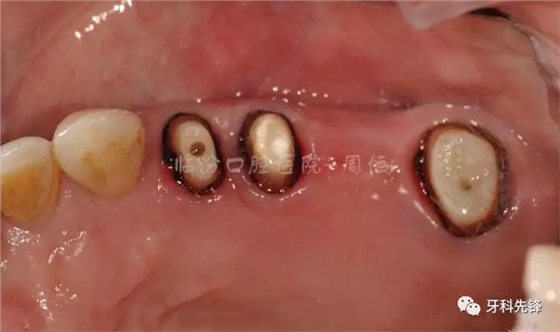

圖9去除腐質(zhì)口內(nèi)照

640.webp (13).jpg